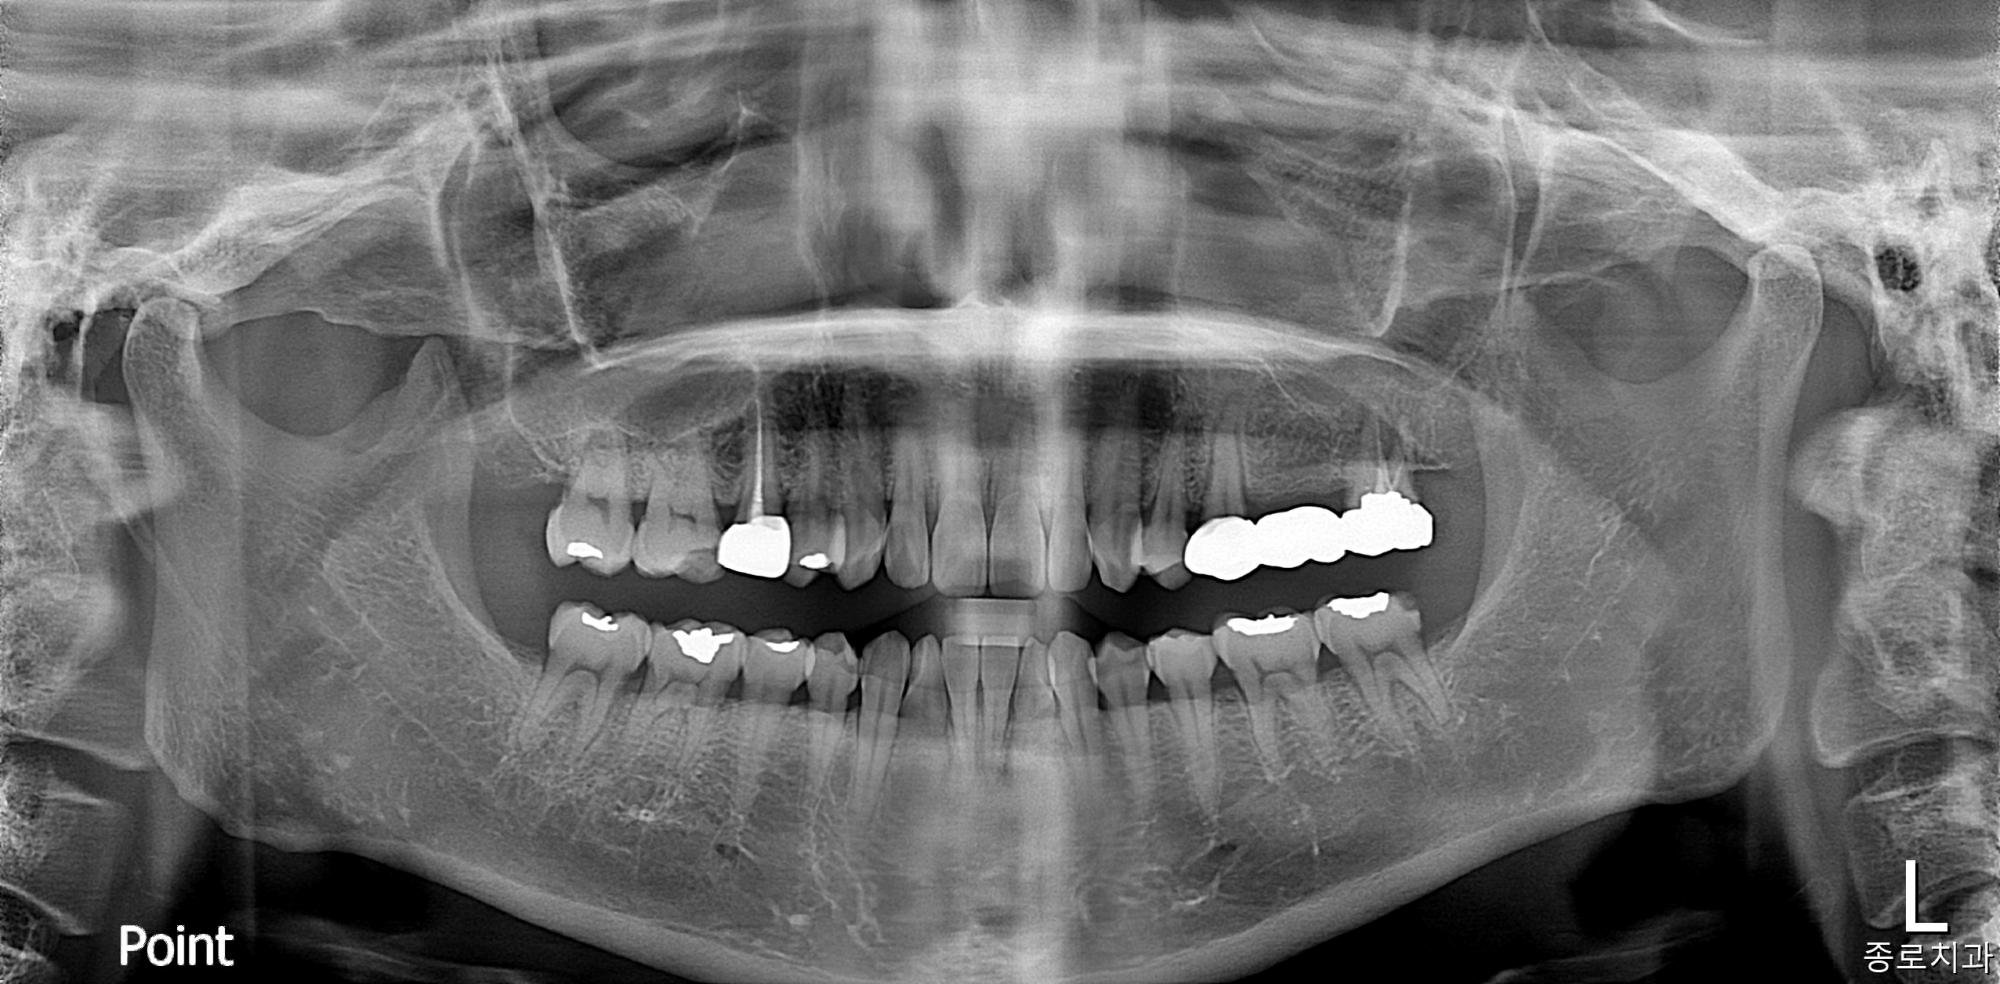

전/후 사진갤러리